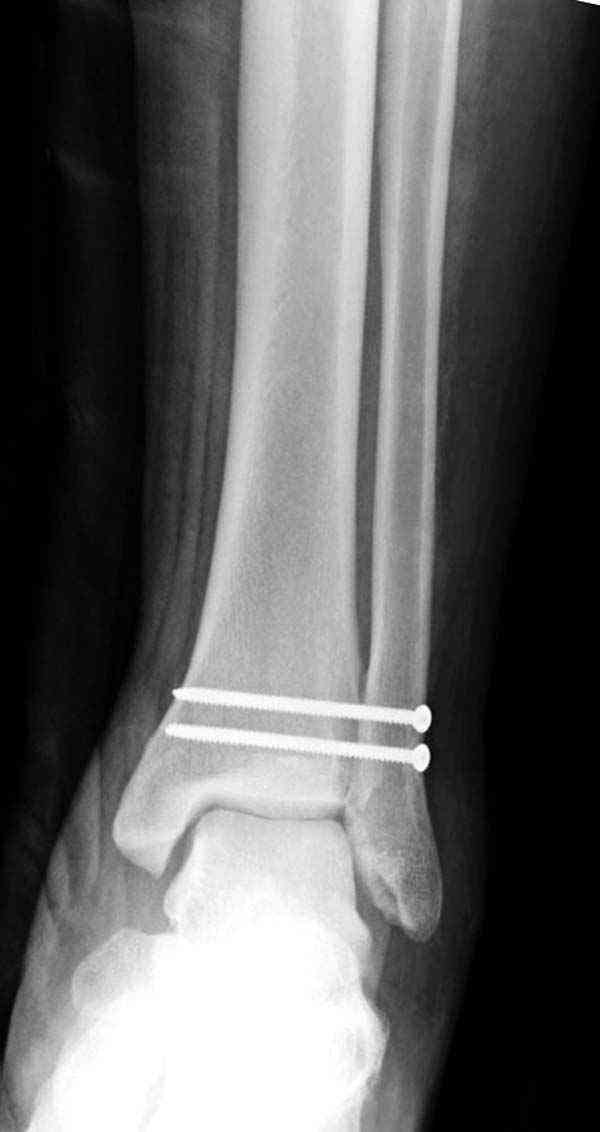

Случай прошлого года:пациентка-молодая ,крупная женщина ,30лет.Травма в начале апреля 2009г-пронационный перелом лодыжек с подвывихом стопы.Ко мне обратилась через 35 дней,прооперирована 22.05.2009г.Внутренняя лодыжка фиксирована по Веберу,наружная реконструктивной пластиной с наложением болта-стяжки.Иммобилизация "сапожок" в течении месяца,затем пригипсовано "стремя".Гипс снят 10.07.2009г

Достаточно быстрое восстановление функции.В октябре 2009г-почувствовала боль,в области рубца над гайкой открылся свищ.На Р-граммах-консолидация переломов и смещение гайки по стяжке.10.11.2009г-конструкции удалены,санация,заживление ран.В настоящее время пациентку ничего не беспокоит.На операции-раскручивание гайки-болталась на конце стяжки.Вопросы:какой механизм раскручивания и что я неправильно сделал?Свои версии:1)в области синдесмоза успела образоваться рубцовая ткань,которая при движении в суставе"пружинила",поскольку голеностопный сустав является спиральным, то и биомеханика подобна кривошипному механизму.2)Реконструктивная пластина не "реконструировалась" по форме лодыжки.Наложил,как есть.То есть подпружинивала сама пластина.Ну,это мои догадки.Что нужно,чтобы избегать впредь таких,пусть и не "страшных"осложнений:Рассверливать через лодыжку область синдесмоза?Ставить шайбу-гровер?Тщательно моделировать пластину?Прилагаю сравнительные снимки-сразу после операции и перед удалением конструкции.

Визуально никаких вопросов по репозиции не было.Да и на основании чего сомнения,что наружная лодыжка не полностью репонирована или прорезалась проволка ???Я не вижу...Снимок после репозиции справа.

Раз ,есть желание посмотреть другую проекцию выкладываю-ну лучшего качества нет...